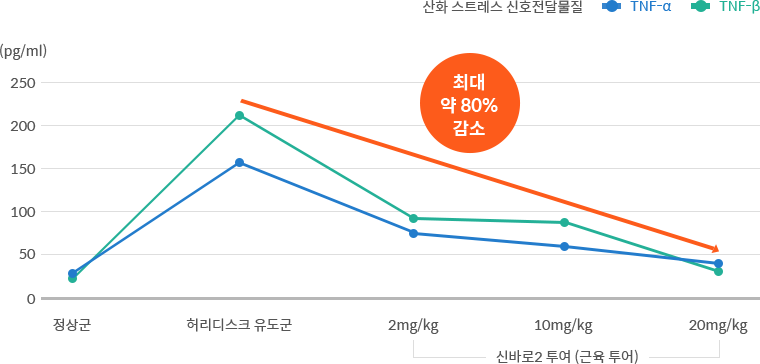

강력한 항염 효과① - 염증 유발 산화 스트레스 최대 80% 감소

허리디스크 상태를 유도한 쥐에 신바로 약침을 투여한 결과, 허리디스크 유도에 의해 증가했던 산화 스트레스 관련 신호전달물질(TNF-α, IL-1β)이 유의미하게 감소했습니다.

- 연구기관 : 자생척추관절연구소, 서울대학교 약학대학 연구팀

- 저널명 : Frontiers in Neurology (SCI급 국제학술지) 2023년 3월호

- 논문명 : Effects of the administration of shinbaro 2 in a rat lumbar disc herniation model